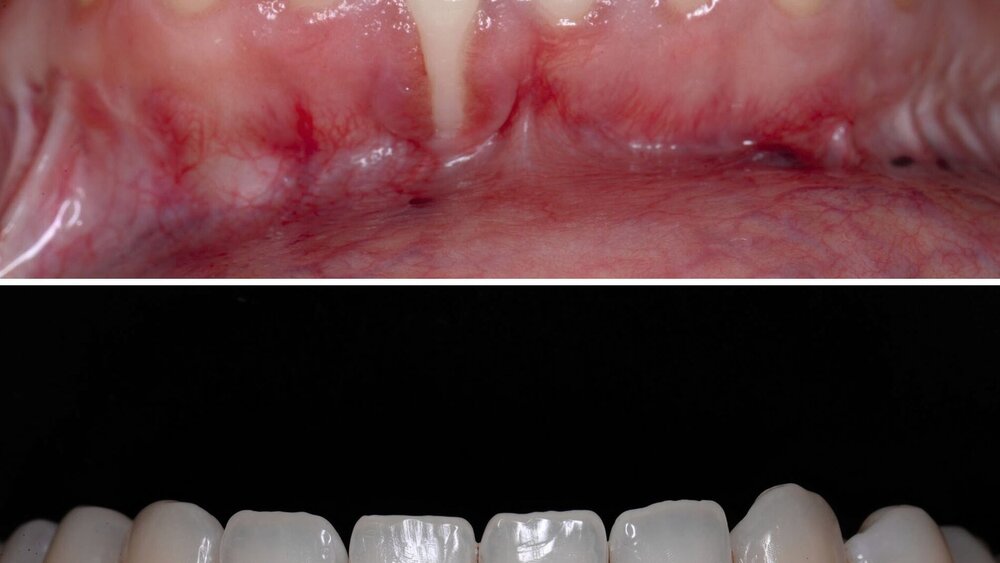

Schon in der Mitte des 20. Jahrhunderts wurden die ersten lateralen Verschiebelappentechniken zur Deckung parodontaler Rezessionen beschrieben. Grupe & Warren veröffentlichten 1955 die erste Beschreibung eines lateralen „sliding flap“ zur Deckung einer singulären parodontalen Rezession [Grupe und Warren, 1956]. Bei dieser Methode wurde das distal von der Rezession gelegene Gewebe einschließlich des bukkalen benachbarten Papillenanteils gelöst und die Gingiva im Bereich der Rezession exzidiert. Anschließend wurde dieser Lappen nach mesial verschoben, so dass der Papillenanteil direkt wieder im Bereich der benachbarten Papille fixiert und die freiliegende Wurzeloberfläche abgedeckt wurde. Großer Nachteil dieser unilateralen Verschiebelappen sind die hohen Rückstellkräfte aufgrund der ausgeprägten Verschiebung in eine Richtung um circa eine Prämolarenbreite. Daher zeigen laterale Verschiebelappen eine hohe Rezidivtendenz mit geringer prozentualer mittlerer Wurzeldeckung von 34 bis 82 Prozent, die zwar durch den zusätzlichen Einsatz eines Bindegewebstransplantats mit 70 bis 98 Prozent deutlich verbessert wird, aber durch die ausgeprägten Spannungen zu einer erhöhten Narbenbildung führt, die auch nach Jahren deutlich sichtbar sein kann (Abbildung 1) [Pagliaro et al., 2003]. Zudem führte die Verschiebung der keratinisierten Gingiva an den Nachbarzähnen nicht selten zu einer parodontalen Rezession an diesen, so dass Grupe in einer weiteren Publikation empfahl, die marginale Gingiva der Nachbarzähne in den Verschiebelappen nicht mit einzubeziehen [Grupe, 1966]. Pfeifer & Heller empfahlen in ihrer Analyse zur Vermeidung von Rezessionen an den Nachbarzähnen anstatt vollschichtiger Lappen teilschichtige Präparationen durchzuführen [Pfeifer und Heller, 1971].

Aus diesem Grund kann die Nelson-Technik dahingehend verändert werden, dass die Läppchen verlängert werden, indem diese am Sulkus der Nachbarzähne vorbeigeführt werden und die Entlastung nicht als senkrechte Inzision, sondern in Form eines runden Rückschnitts zur Rotation der Lappen geführt wird (Abbildung 2). Dies erleichtert auch die vollständige Deckung des OP-Gebiets, so dass keine sekundäre Granulation im lateralen Bereich erforderlich ist (Abbildung 2d). Auch bei guter Heilung zeigt sich aber eine ausgeprägte Narbenbildung direkt im Bereich des gedeckten Zahnes, insbesondere bei singulären Rezessionen. Zudem kommt es zu deutlichen Veränderungen von Textur und Farbe im Bereich der mukogingivalen Grenze, die ebenfalls das ästhetische Ergebnis stark beeinträchtigten (Abbildung 2e).